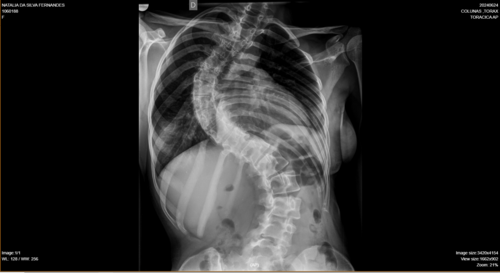

Olá, me chamo Natália da Silva Fernandes, tenho 21 anos, moro na cidade de Ji-Paraná, no estado de Rondônia. Fui diagnosticada com escoliose e venho na busca de um tratamento pelo SUS há um tempo, mas não obtive retorno até o presente momento. Passei por algumas consultas com ortopedistas do SUS, peguei encaminhamentos para passar com um neorocirurgiao e depois de um longo período de espera, consegui uma consulta com um neorocirurgiao do SUS, quando ele viu meu estado de saúde ele disse q a única solução é fazer a cirurgia, como na cidade não tem estrutura para realizar a cirurgia através do SUS, peguei mais um encaminhamento para consultar pela segunda vez por outro neurocirugiao, mas na cidade de Porto Velho, e nisso fiquei no aguardo desse agendamento mas até o momento nenhum retorno do SUS, ou seja, nenhum pedido de agendamento de cirurgia, apenas consultas, é um processo burocrático conseguir uma cirurgia pelo SUS, pois tem uma lista de pacientes na espera por vaga. Devido à demora do SUS , recorri a um neurocirurgião particular e o diagnóstico que recebi foi o mesmo, necessito fazer a cirurgia com urgência.Atualmente, me encontro num quadro doloroso, minha escoliose está com 86° de encurvatura, sinto dores constantes, tenho dificuldade em andar e às vezes dificuldade em respirar, porque são dores muito fortes. Para dormir, é uma luta constante para achar uma posição que dê menos desconforto . Diante de todo esse processo doloroso, e todo o tempo que venho recorrendo ao SUS e não obtendo uma solução favorável, a preocupação aumenta cada dia, pois não tenho condições de custear nem a cirurgia, nem o tratamento pós-cirúrgico. Foi então que surgiu a solução de fazer a vaquinha. A cirurgia fica em média de 250 mil reais com o tratamento pós-cirúrgico. Deixo na descrição os laudos e exames que venho realizando como transparência da minha situação.Toda ajuda é bem-vinda!Ajude-me compartilhando em suas redes sociais. Deixarei minha rede social para entrarem em contato comigo para mais informações: @_fe3_n47ou acesse o link abaixo e vá direto ao meu perfil.https://www.instagram.com/_fe3_n47?igsh=MXA1bDEzNW53YzZ5NA==